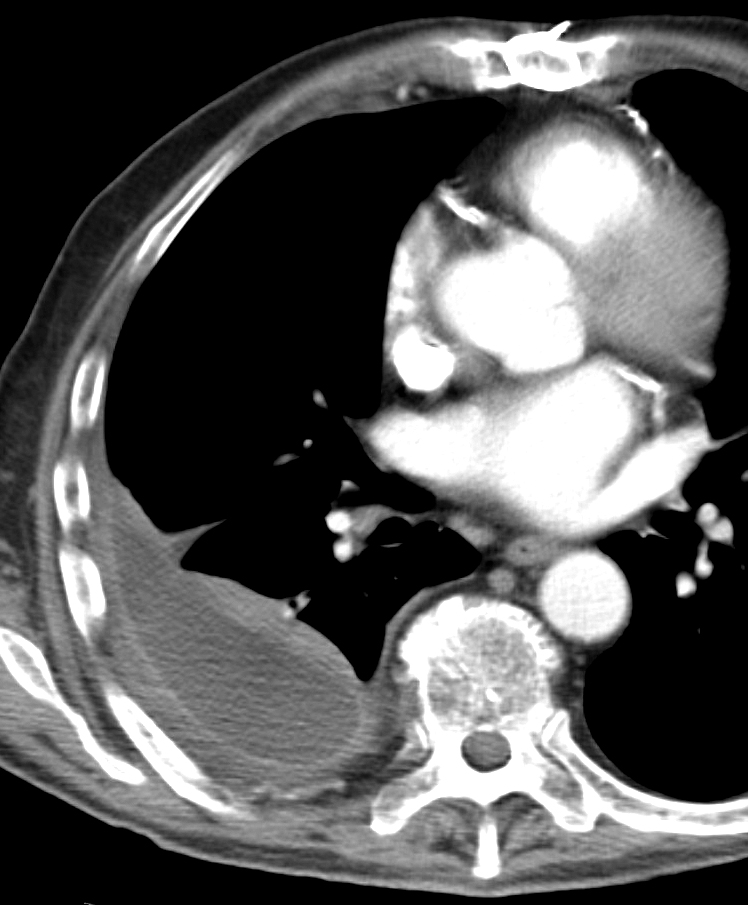

Gallery Pleural empyema 2 CT

empyema 2 CT